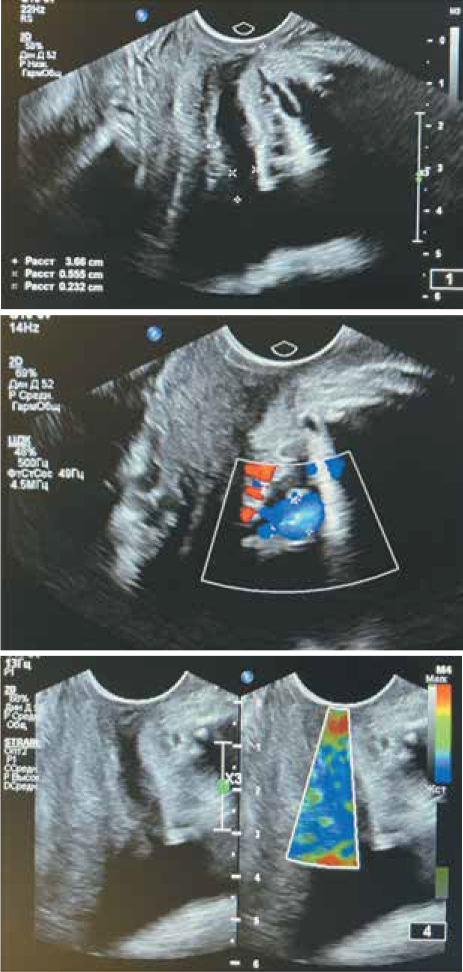

Расширение мочеиспускательного канала до 6,5 мм до лечения и нарушение кровотока в стенках по типу спазма мелких сосудов было выявлено у 38/44 (86,4%) женщин основной группы (рис. 2). После комплексной терапии с использованием БАД «Менсе» небольшое расширение мочеиспускательного канала было обнаружено у 15/44 (34,1%) пациенток, у остальных женщин мочеиспускательный канал был сомкнут (рис. 3).

Рис. 2. УЗИ мочевого пузыря, уретры, сосудов малого таза и парауретрального сплетения (пациентка основной группы до лечения)

При ЛДФ стенки мочевого пузыря и слизистой уретры у пациенток обеих групп получены данные, указывающие на достоверное снижение капиллярного кровотока в тканях на фоне рецидивирующей инфекции нижних мочевых путей и менопаузы до лечения, отмечено падение перфузии тканей, а также сатурации кислорода (рис. 4).

Анализируя полученные ЛДФ-граммы, отмечено превалирование влияния симпатического тонуса нервной системы, чем объясняется спазм сосудов микроциркуляторного русла в стенке мочевого пузыря и уретры и снижение амплитуд осцилляций кровотока в нейрогенном диапазоне (0,02-0,052 Гц).

При этом миогенный компонент сосудистого тонуса микроциркуляторного русла стенки мочевого пузыря и уретры, обусловленный состоянием гладкомышечных структур сосудов, остается неизменным (диапазон 0,07-0,15 Гц). Это объясняет достаточно быстрое купирование ангиоспазма в стенках уретры у пациентов основной группы, где использовалась комплексная терапия.

Межгрупповая сравнительная характеристика нарушений микроциркуляции в стенке мочевого пузыря и уретры выявила значимое сохранение микроциркуляторных нарушений у пациентов контрольной группы на фоне менопаузы как после 1-го месяца, так и после 6 месяцев наблюдения, по сравнению с пациентками основной группы, где в комплексной терапии применена БАД «Менсе» (рис. 5), обладающая положительным влиянием на микроциркуляцию (табл. 4).